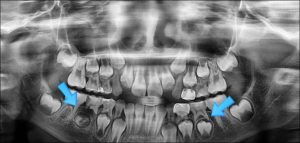

인덕원 치아치료 아프기 전에 관리가 중요합니다.

인덕원 치아치료 아프기 전에 관리가 중요합니다. 안녕하세요.인덕원 믿음치과 대표원장 손동근입니다. 치과 진료를 하다 보면 “조금 더 일찍 치료받으셨다면 좋았을 텐데요”라는 말씀을 드리게 되는...